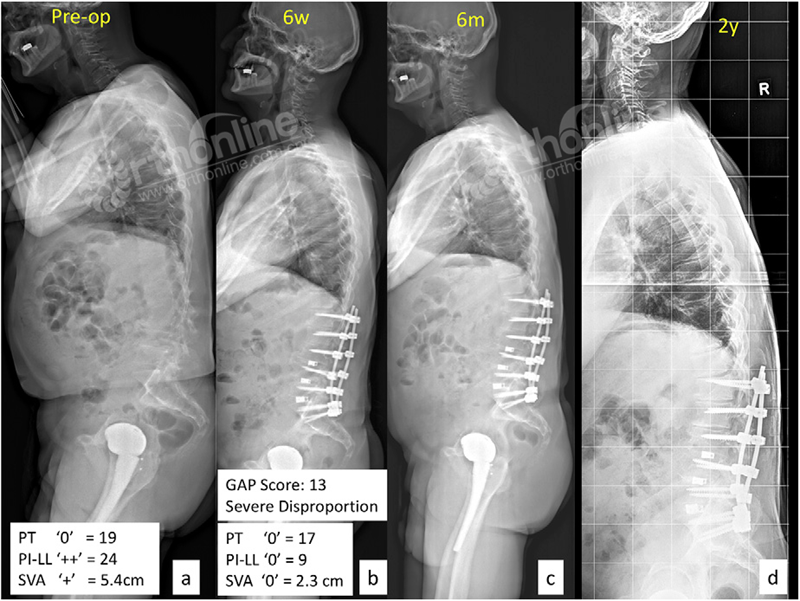

图7.一例60岁女性脊柱畸形患者(PI:26°),术前(A),术后6周(B),术后6月(C)和术后2年(D)。按Schwab分型,术前PT:19°(),PI-LL:24°(++),SVA:5.4cm(+)。术后6周矫形至PT:17°(),PI-LL:9°(),SVA:2.3cm ()。但是按GAP评分系统患者为13分(重度失平衡脊柱)。术后2年患者出现进展性PJK